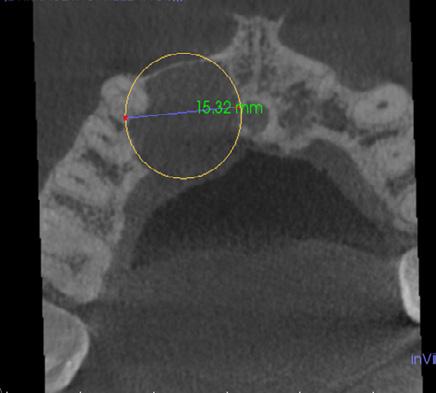

Tratamiento combinado de un quiste radicular de larga data: A propósito de un caso clínico

Combined treatment of a long-standing radicular cyst: A clinical case report

Javier BorisAdrián Burgos, Johanna Valentina Virreyra Bloomfield..........................................................133-142